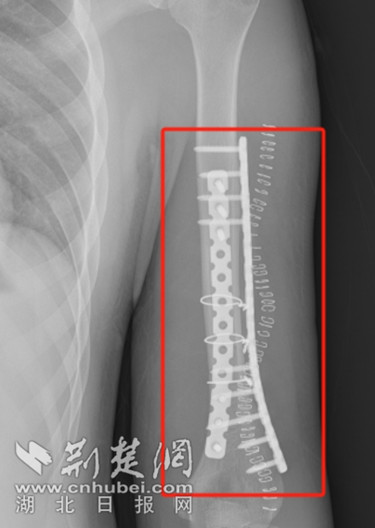

由于肱骨下段骨折涉及关节面、骨碎片和周围软组织的损伤,肱骨下段附近又有重要的神经和血管,为了保证手术顺利完成,武汉市普仁医院骨关节外科主任张国华带领专家团队为小王进行了充分评估并制定了个性化的手术方案,在与小王与刘女士进行充分沟通后,于4月4日上午为其行左肱骨骨折切开复位钢板内固定术,手术全程十分顺利,术后小王精神状态明显好转。

术后复查X线拍片显示:骨折对位线可,内固定物正常 通讯员 供图